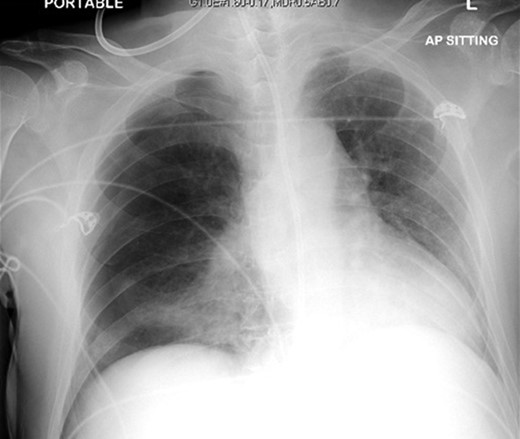

A 72-year-old male was admitted to a tertiary hospital following a cerebrovascular accident. His neurological deficits were global aphasia, dysphagia and right hemiplegia. He underwent a routine NGT change with a small bore NGT by an experienced nurse on Day 2 of admission. The nurse was unable to obtain any aspiration from the newly inserted NGT and a chest radiograph was done to confirm placement as per hospital protocol. This showed a malpositioned NGT, traversing the right main bronchus with the tip of tube in the right costophrenic sulcus (Fig. 1). She was alerted about the chest radiograph findings and removed the tube before reinserting another NGT. The subsequent aspiration from the NGT had a pH of 7, hence another chest radiograph was done which now demonstrated a right pneumothorax (Fig. 2). The pneumothorax was likely due to intrapulmonary placement of the earlier NGT.

Chest x-ray showing the nasogastric tube, traversing the right main bronchus with the tip in the right costophrenic sulcus.